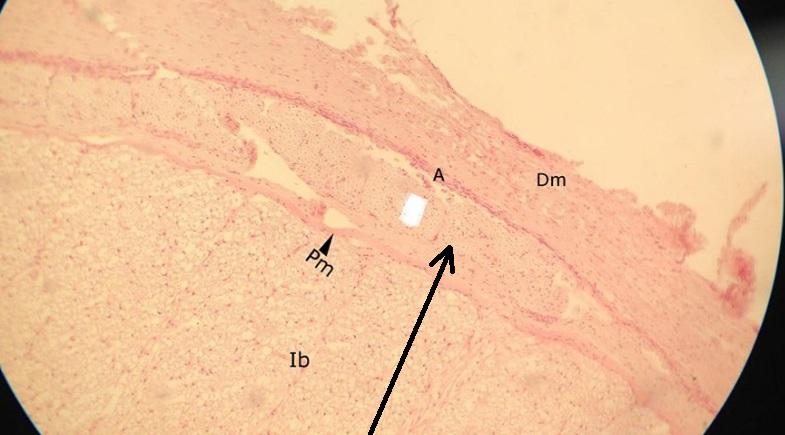

Pytanie 178

więzadło ząbkowane (rdzeń kręgowy)

Pytanie 179

pajęczynówka (rdzeń kręgowy)

Pytanie 180

korzeń nerwu rdzeniowego (rdzeń kręgowy)